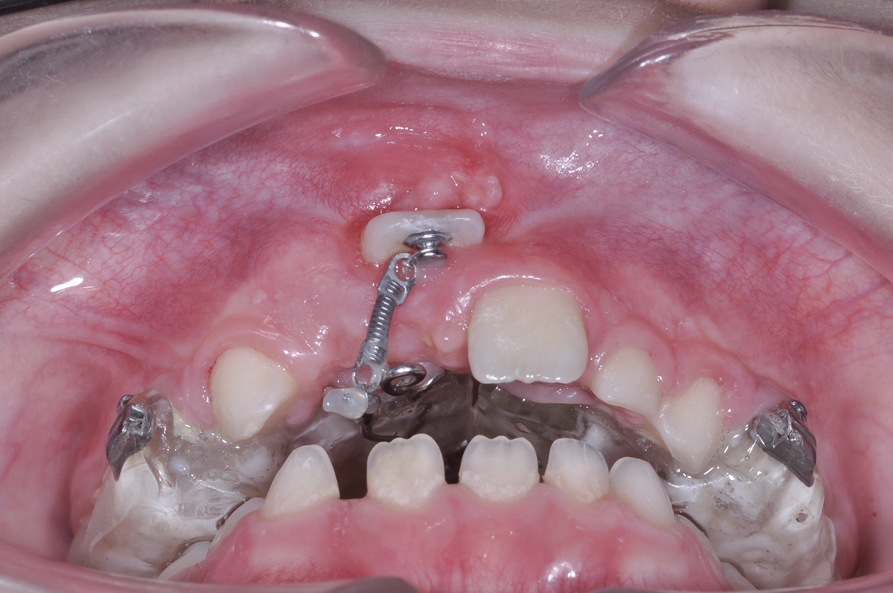

The maxillary right permanent centralincisor had a delayed eruption of 1½ years compared to its homologous incisor, and it was anteriorly displaced due to insufficient space in the premaxilla. Removal of the maxillary deciduous canines was indicated to unravel the crowding. An apically positioned flap of the impacted right central incisor was made to facilitate its eruption (Figure 5 and Figure 6). The case was worked up to plan an active phase l treatment, consisting of palatal expansion and the use of sectional fixed appliances in the upper arch. A transverse deficiency without posterior crossbite was identified, and therefore palatal expansion with a bonded expander was planned to widen the premaxilla (Figure 7 and Figure 8). A two-by-four fixed appliance system (brackets in the four maxillary anterior teeth and bands on the maxillary first molars) was used to align the maxillary teeth. The gingival margin of the retained maxillary right central incisor was slightly more apical than the left one, which erupted as expected (Figure 9 and Figure 10). Figure 11 shows a panoramic radiograph taken after completion of phase 1 treatment.

In reviewing this case more closely, the sequence usually starts with a space opening (Figure 12 through Figure 14). Palatal expansion is generally performed even without the presence of a posterior dental crossbite, as many patients with impacted maxillary central incisors are deficient in the development of the anterior portion of the maxilla.7,11 The use of sliding mechanics with open coils in conjunction with simple fixed systems is preferred to removable appliances since they deliver a light, continued force instead of an intermittent force.7 Interarch mechanics allow space to be gained for either the natural eruption or the surgical/orthodontic traction of the impacted maxillary central incisor.7 After palatal expansion, rigid structures, such as fixed transpalatal arches soldered to upper first molar bands, might first be used to anchor the active traction of the impacted tooth. Later, orthodontic fixed appliances reportedly have been used in the maxillary anterior to detail the position of the maxillary central incisor in the arch.11 Frequently, power arms are incorporated into palatal expanders.12 Fixed systems initially employ flexible nitinol wires and round stainless-steel wires. After initial leveling, rectangular stainless-steel wires have been used as part of several protocols to produce torque and place the roots of the resolved impacted central incisor in the proper position in its apical base.3,7,13 Orthodontic traction is conducted with different systems based on the preference of the clinician.3,7,10

Fig 12. After expansion of the maxillary arch, the modified palatal expander was used for traction of the impacted maxillary right central incisor. Fig 12: Palatal expansion to gain space in the premaxilla for the impacted maxillary right central incisor. Fig 13: Traction of the impacted maxillary right central incisor through a palatal orthodontic attachment and the use of a power arm incorporated in the expander. Fig 14: Detailing the position of the impacted maxillary right central incisor with orthodontic fixed appliances.

Fig 13. After expansion of the maxillary arch, the modified palatal expander was used for traction of the impacted maxillary right central incisor. Fig 12: Palatal expansion to gain space in the premaxilla for the impacted maxillary right central incisor. Fig 13: Traction of the impacted maxillary right central incisor through a palatal orthodontic attachment and the use of a power arm incorporated in the expander. Fig 14: Detailing the position of the impacted maxillary right central incisor with orthodontic fixed appliances.